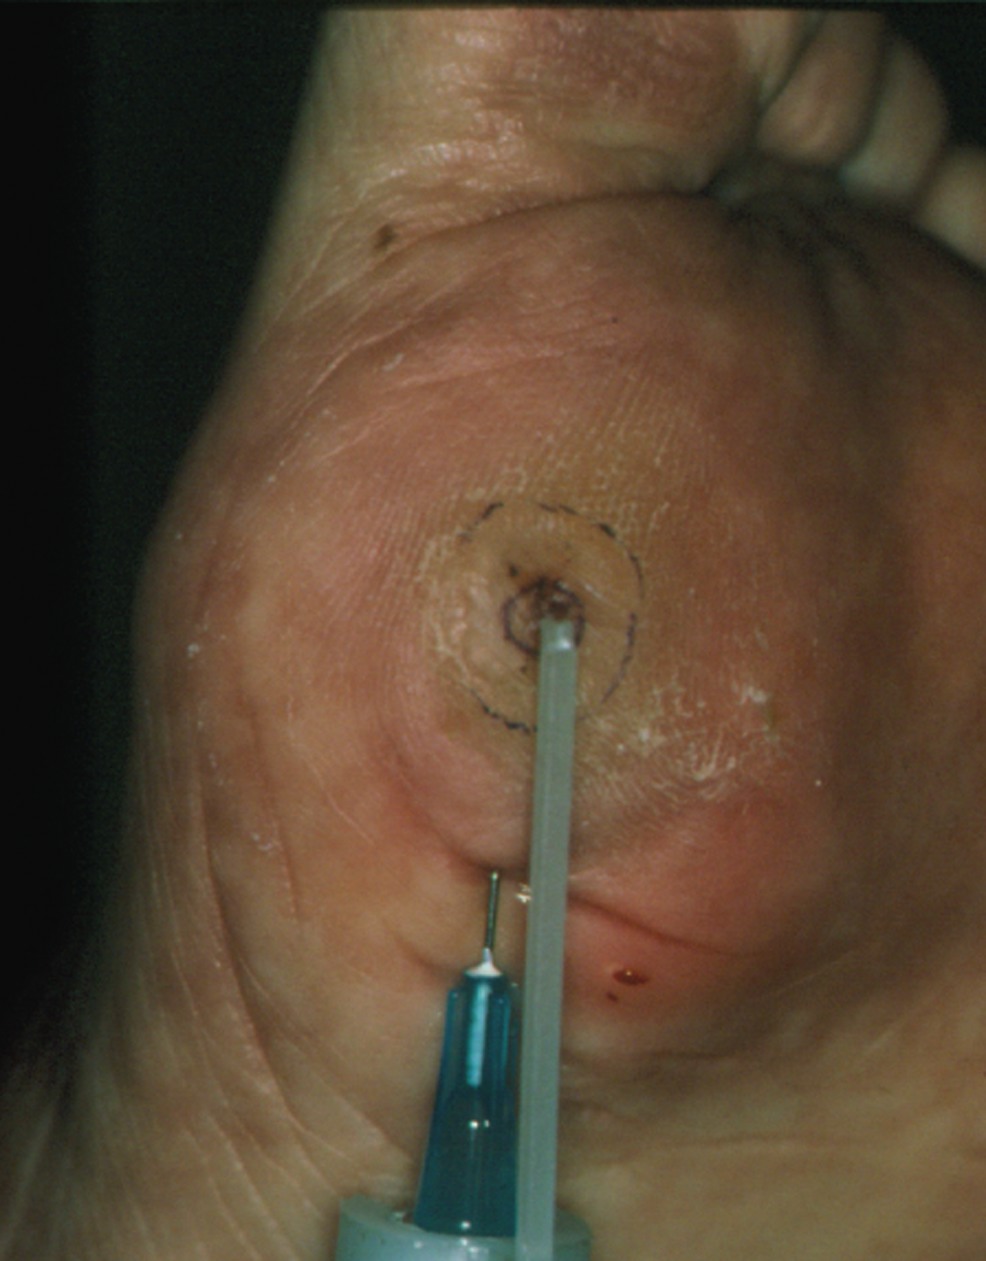

The present tenet for preventing wounds therefore focuses on the redistribution of pressure. One would customarily do this with therapeutic footwear and accommodative orthotics. The ability to easily remove prescribed footwear eliminates the element of “forced adherence.” A study that evaluated the activity of patients with diabetic foot ulcerations and adherence to their pressure offloading device noted that patients wore their prescribed offloading modality for only 28 percent of their total daily activity.24 The data reported above may be explained at least partially by another study conducted in patients with diabetes who are at high risk for foot amputation. In an evaluation of the magnitude and location of activity of people with diabetes in this high-risk population, results suggested that patients may be at least as active at home as they are outside their home.25 While 85 percent of the patients in that study indicated that they wore their physician-approved shoes most or all of the time while outside the home, only 15 percent continued use of the shoes while at home.25 It may therefore be postulated that patients with neuropathic ulcers who wear removable offloading devices may perceive the home environment as safe and be less adherent to wearing their devices. By injecting a tissue volumizing agent beneath a plantar prominence, it may be possible to create an internal accommodative orthotic effect that follows the patient everywhere he or she goes, and acts to mitigate pressure 24 hours a day. Accordingly, tissue augmentation may have the benefit of adequate offloading as well as adding an element of “forced compliance” to the prescribed course of pressure reduction. Further, patients may also benefit from certain prophylactic interventions, including evaluation for surgical interventions to alter their biomechanics and loading. It has been well established that plantar pressure is directly proportional to plantar tissue thickness.26,27 Fat pad atrophy is common among people with diabetes, particularly in the forefoot.28,29 Clearly, augmenting this high-risk area with a biocompatible, viscoelastically robust substance might have the benefit of mitigating pressure and potentially reducing the risk for ulceration. Researchers, who have studied the use of substances such as silicone in the foot, suggest there is significant improvement in soft tissue thickness and subsequent profound reduction in plantar pressure.

Sol W. Balkin, DPM, who reportedly has the most experience with silicone foot injections in the U.S., reported on 1,439 silicone injected patients.30-33 Thirty-eight patients had diabetic neuropathy with 41 ulcers and 16 pre-ulcerative lesions. The patients received injections of silicone in doses of 0.10 to 0.25 mL at the site of ulceration or plantar prominence at one- to four-week intervals to a mean total of 1.65 mL. All 41 ulcers healed initially while 30 (73 percent) remained healed at a mean follow-up of 6.3 years. None of the 16 pre-ulcerative lesions recurred. There were no reports of infection, rejection or allergy. Balkin and colleagues obtained postmortem specimens from deceased patients (unrelated mortality) and evaluated them at a mean of 14 years (range of one to 29 years) post-silicone implantation. Histological analysis of these specimens revealed noninflammatory fibrosis and histiocytic phagocytosis. In rare instances, asymptomatic fluid migration occurred and required surgical removal. In the United Kingdom, Van Schie, et. al., performed a randomized, double-blind, placebo-controlled (saline) trial on 28 diabetic neuropathic patients with high peak plantar pressures under metatarsal heads.29 Peak plantar pressures were reduced by 232 kPa in the silicone group and by only 25 kPa in the saline group. The researchers found that plantar soft tissue thickness, measured by ultrasound, increased by 1.8 mm in the silicone treated group versus 0.1 mm in the control group. Unfortunately, in the U.S., availability/production and medical legal concerns have made silicone a less than realistic choice for implementation in a widespread setting. Other products, such as poly-L-lactic acid and hyaluronan, have shown promise as fat pad replacements/dermal fillers.34,35 Poly-L-lactic acid appears to have direct promise in this regard as its current primary indication is for facial lipoatrophy commonly associated with the human immunodeficiency virus (HIV).

Scholl’s Center for Lower Extremity Ambulatory Research (CLEAR) is currently conducting a trial on 80 patients with diabetic neuropathy with pre-ulcerative callus under metatarsal heads or the hallux for randomization and injection of either PLLA (Sculptra) or placebo. Patients will receive three injections spaced two weeks apart. Researchers will follow them for 12 months and record dynamic plantar pressure pre- and post-treatment. These data will be compared to the van Schie data on silicone injections in diabetic feet to determine if there are any medium or long-term effects.29 Soft tissue augmentation of the high-risk plantar diabetic foot with fillers may soon be a promising prophylactic technique to increase plantar soft tissue thickness and create an internal orthotic effect that can ultimately reduce the risk for ulceration. The results of this randomized controlled study will help assess the biocompatibility of dermal fillers in the plantar foot and their efficacy in pressure mitigation and ulcer prevention. Dr. Wu is the American Podiatric Medical Association Senior Fellow at the Center for Lower Extremity Ambulatory Research (CLEAR) at the William M. Scholl College of Podiatric Medicine at Rosalind Franklin University of Medicine and Science in Chicago. Dr. Rogers is a Research Fellow at the Center for Lower Extremity Research (CLEAR) at the William M. Scholl College of Podiatric Medicine at Rosalind Franklin University of Medicine and Science. Dr. Bevilacqua is a Research Fellow at the Center for Lower Extremity Research (CLEAR) at the William M. Scholl College of Podiatric Medicine at Rosalind Franklin University of Medicine and Science. Dr. Armstrong is a Professor of Surgery, Chair of Research and Assistant Dean at the William M. Scholl College of Podiatric Medicine at Rosalind Franklin University of Medicine in Chicago. He is the Director of the Center for Lower Extremity Ambulatory Research (CLEAR) at the aforementioned university and is the Co-Chair of the Diabetic Foot Global Conference (DFcon.com). For further reading, check out the archives at www.podiatrytoday.com.